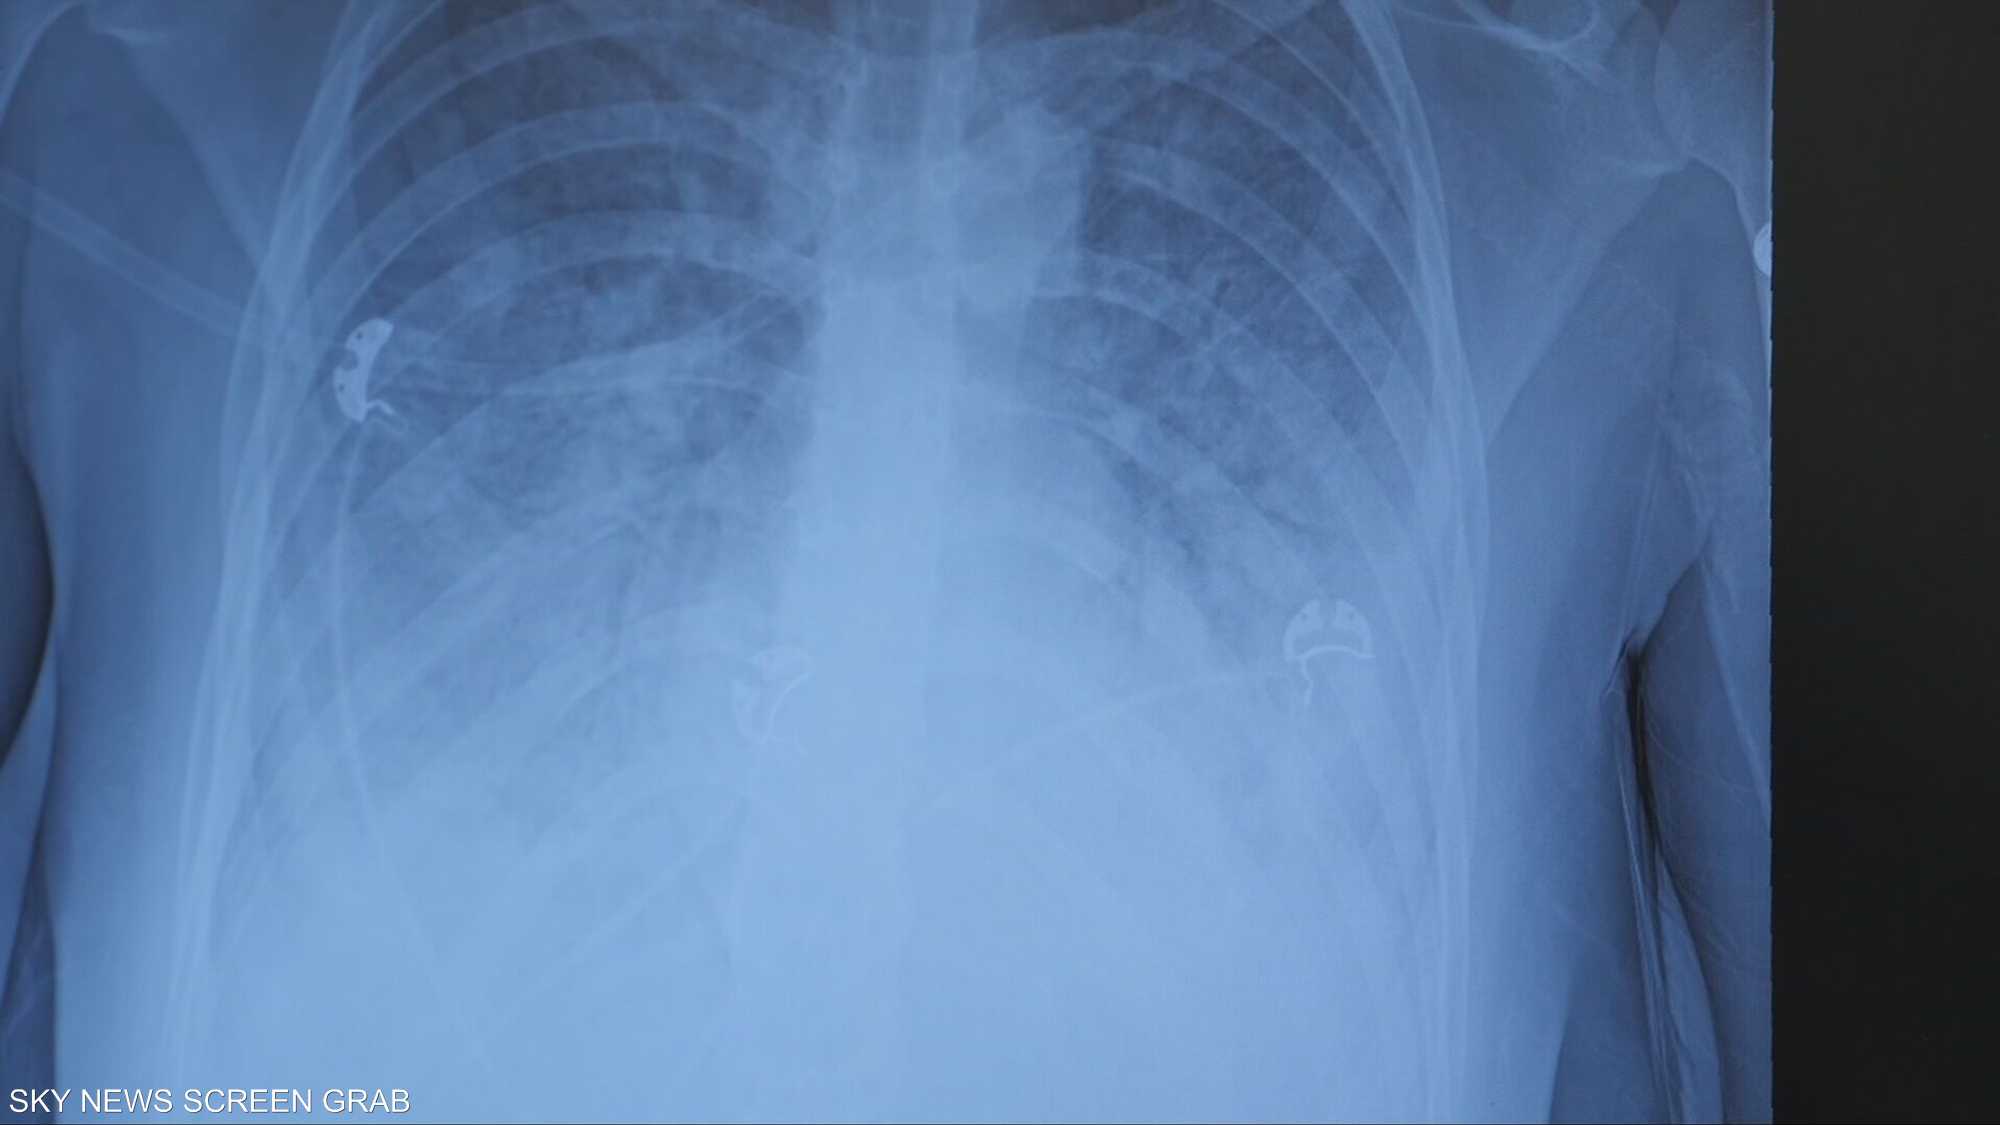

شاب أردني يفقد رئته بسبب الفيب ويدخل رحلة تنفس صناعي

"رئة الفشار" مصطلح أصبح ترندا على منصة تيك توك، بعد إطلاق حملة توعية قادها عدد من الشباب والمؤثرين للحديث عن مرض "بوب كورن لونج"، أو ما يعرف بـ"رئة الفشار"، الناتج عن استخدام أجهزة "الفيب".